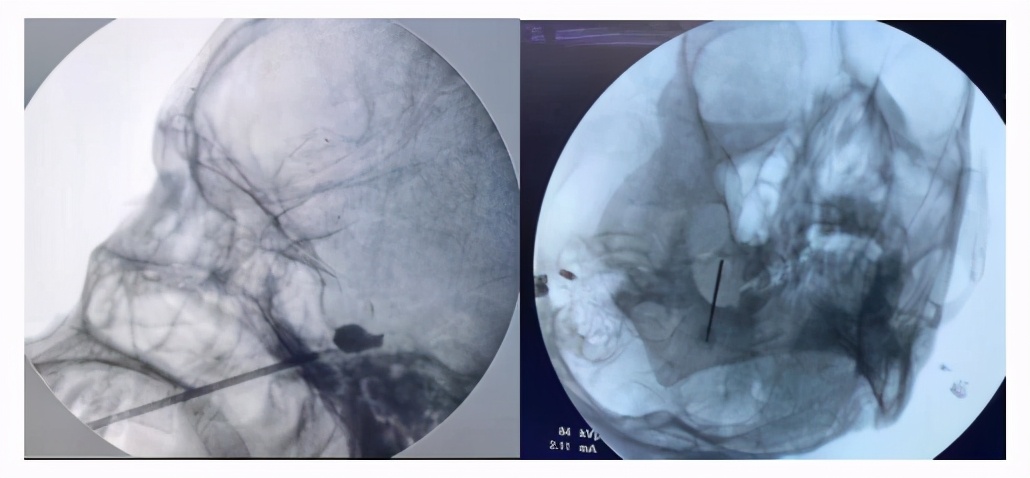

术中,主治医生为何阿姨行L1、L2、L3S神经根脉冲调控治疗,完全复制出疼痛症状。

由于何阿姨之前做过开放手术,腰部软组织瘢痕增生明显,正常结构紊乱,给穿刺过程带来极大的困难。